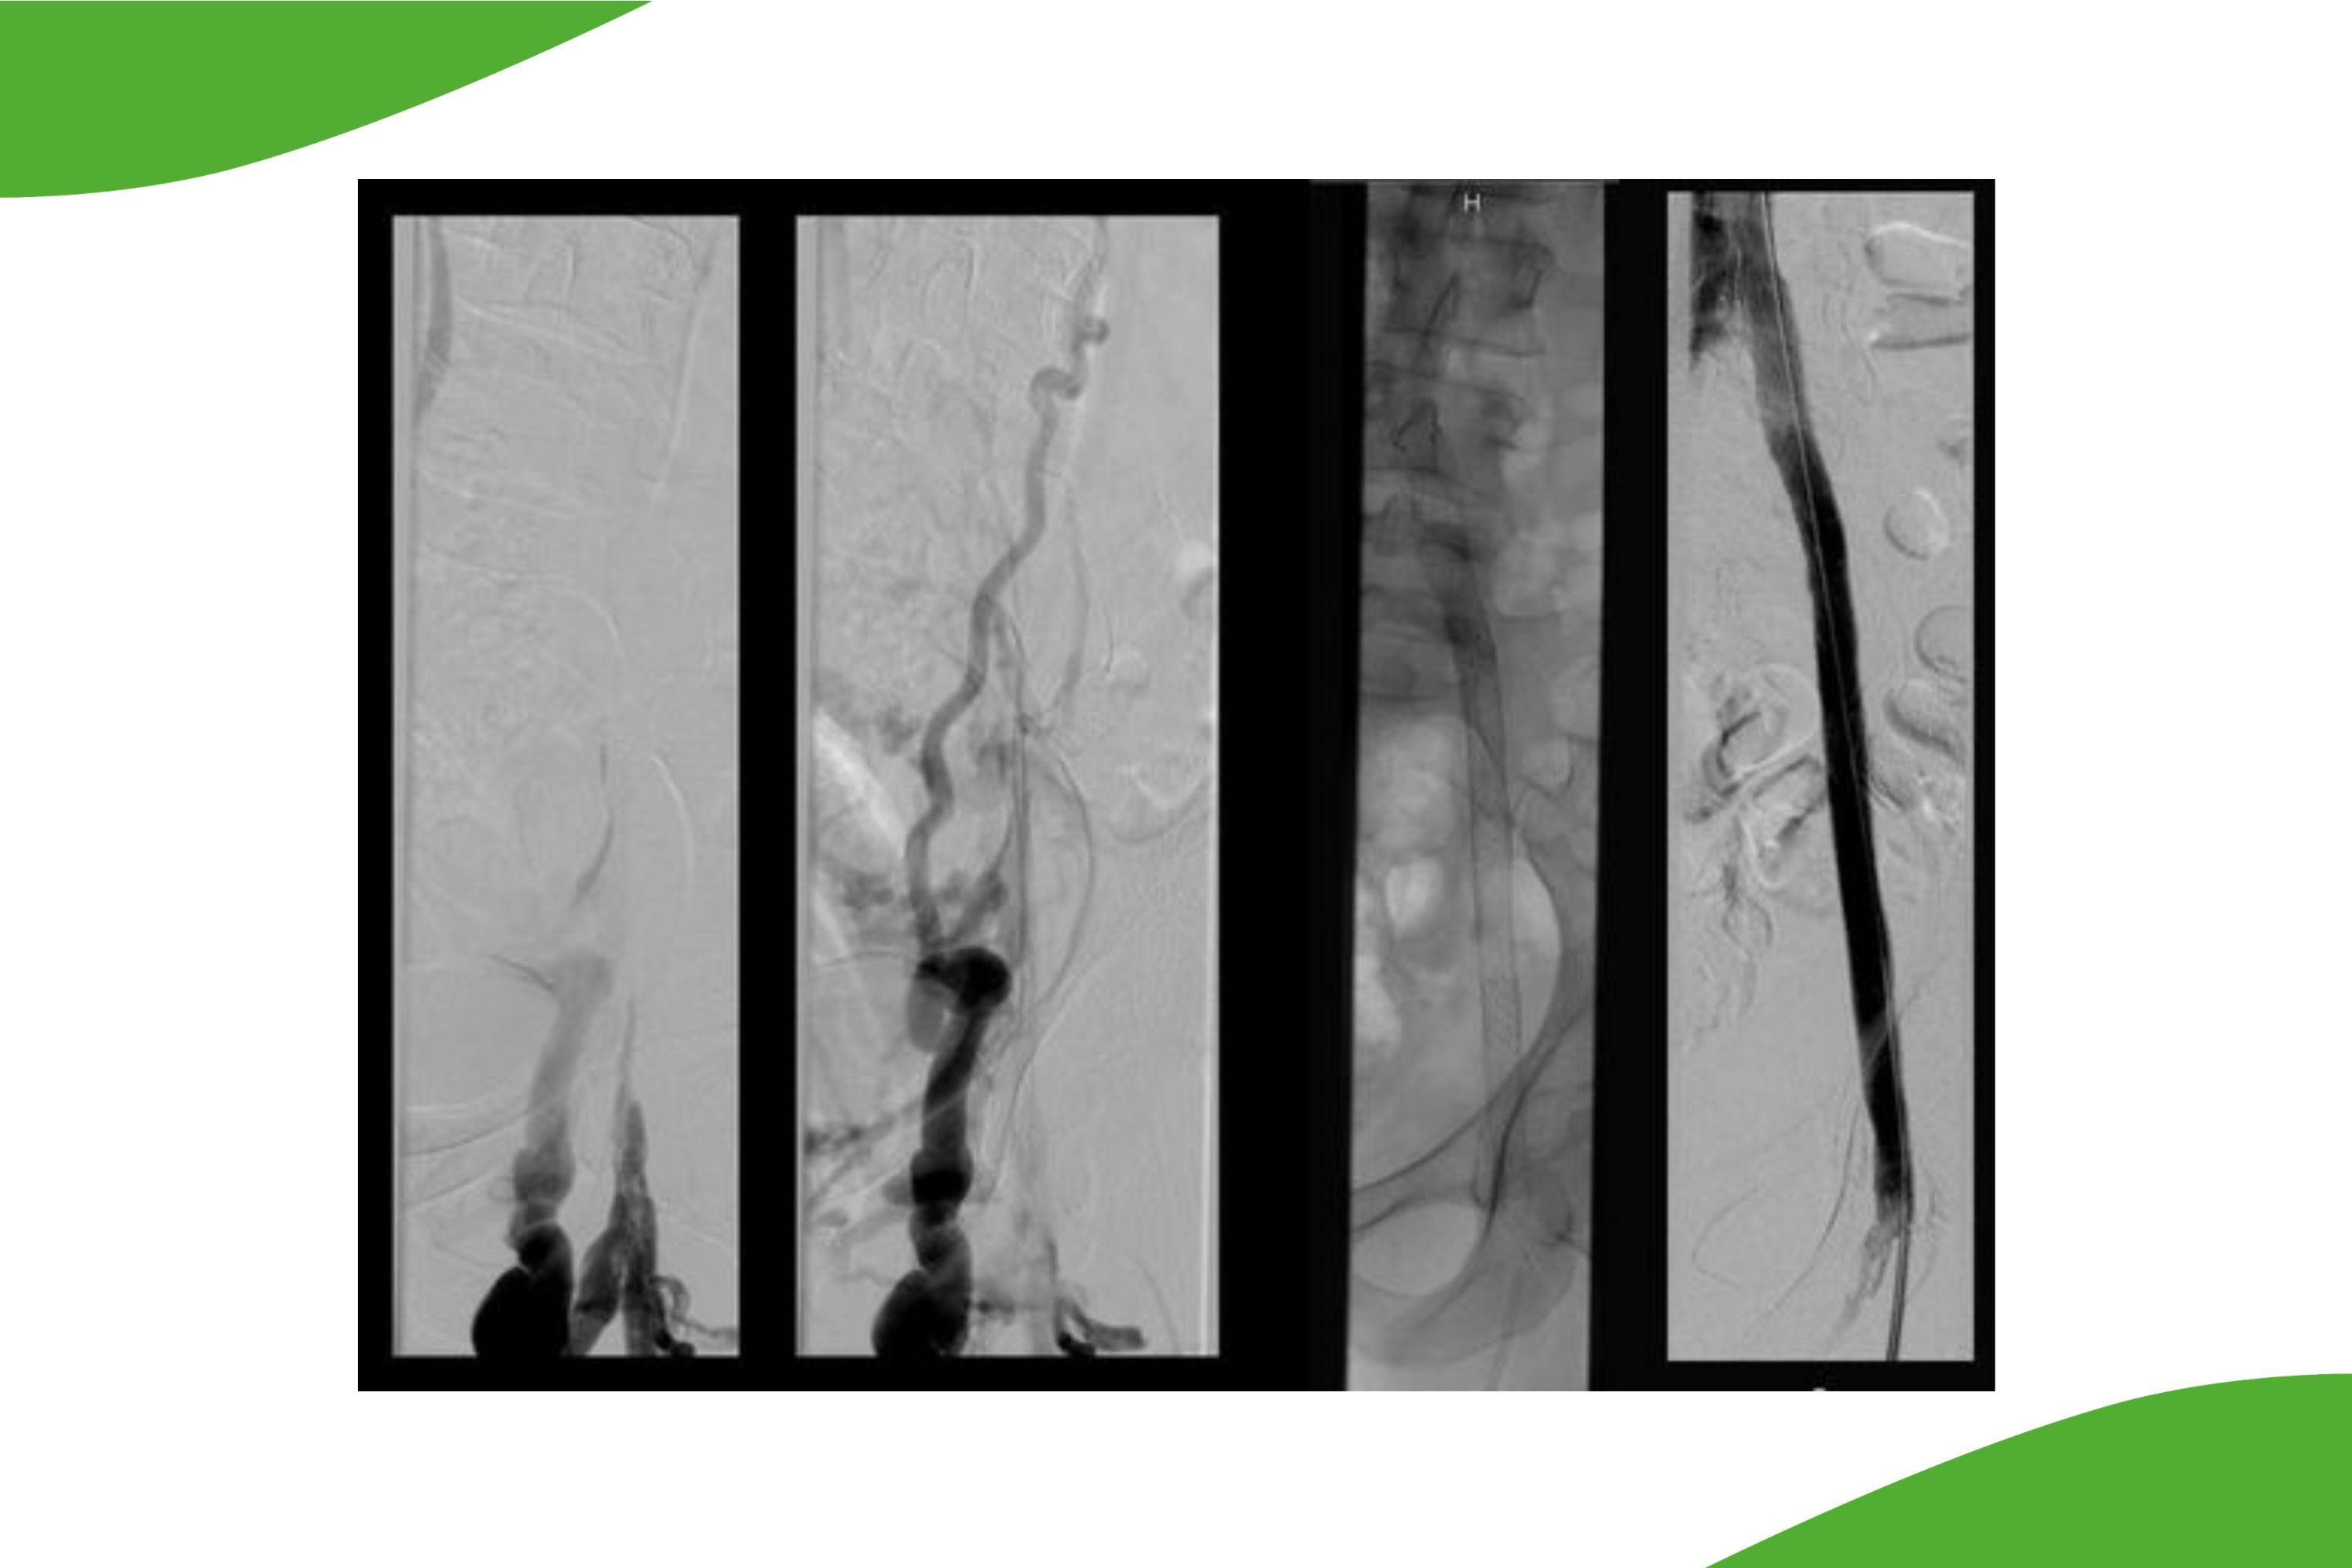

Durch Einsatz von sehr kleinlumigen Kathetersystemen ist heutzutage auch die Behandlung der kleineren Unterschenkelgefäße bis auf Höhe des Fußrückens möglich. Insbesondere bei Patienten mit drohender Fußamputation kann hier durch eine Rekanalisation der Unterschenkelgefäße eine verbesserte Durchblutungssituation erreicht werden, um eine Fußamputation möglichst zu vermeiden. Für eine solche Behandlung sind spezielle dünnlumige und langstreckige Ballonkatheter erforderlich. Am Klinikum Saarbrücken wird in Zusammenarbeit mit den Kollegen der Gefäßchirurgie regelmäßig auch die Rekanalisation von Unterschenkelgefäßen durchgeführt. Dabei kann es auch erforderlich sein, nicht nur ‚von oben‘, also entlang des Blutstroms vorzugehen, sondern wir sind mittlerweile auch in der Lage, vom Fußrücken rückwärts gerichtet sogar langstreckig vollständige Verschlüsse zu behandeln.

Grafische Darstellung der Unterschenkelgefäße: Die Abbildungen zeigen links die Gefäßverschlüsse sowie rechts nach perkutaner transluminaler Angioplastie (PTA) und Stentimplantation. Nach dem Eingriff ist die Gefäßausstrombahn wiederhergestellt.